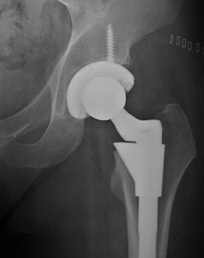

The Ortho Chandigarh offers a range of diagnostic, surgical and rehabilitation service that include Orthopaedic Surgery, Joint Replacement, Spine Surgery, Hand Surgery, Foot & Ankle Surgery, Sports Medicine, Physical Medicine and Rheumatology, assuring a better quality of life at work and at play.